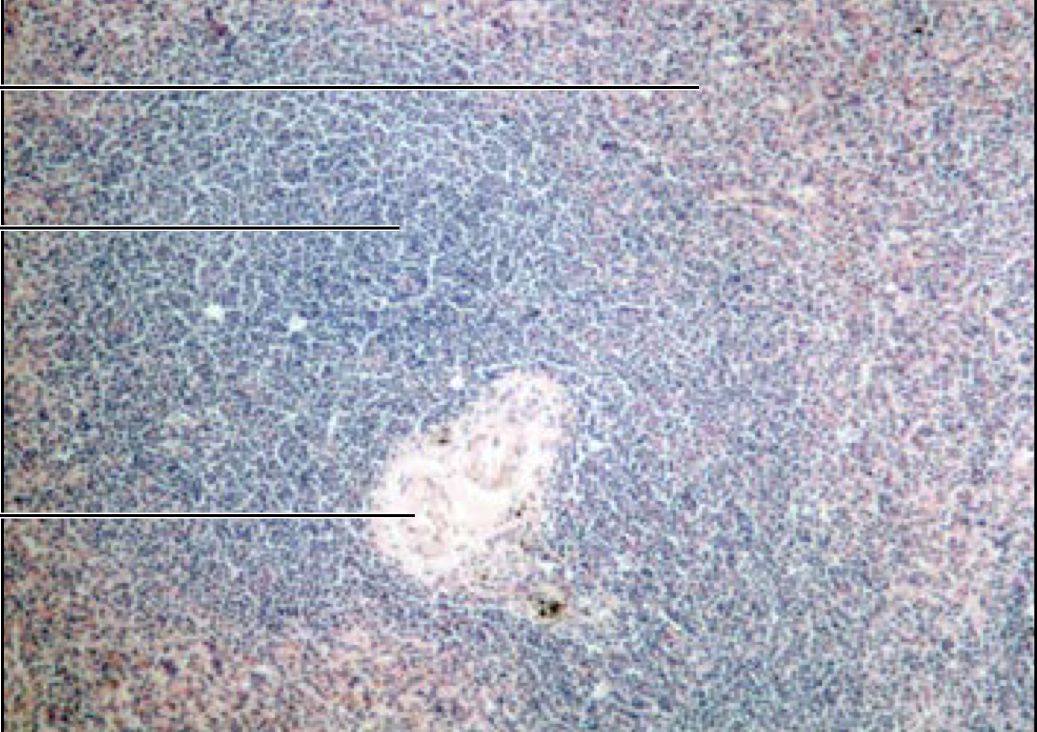

term image

Lymph node

Spleen

white pulp = blue

red pulp = red

what disease is this?

Hodgkins granuloma - cancer of lymphatic system. can lead to breakdown of splenic pulps

Reed-Sternberg cells